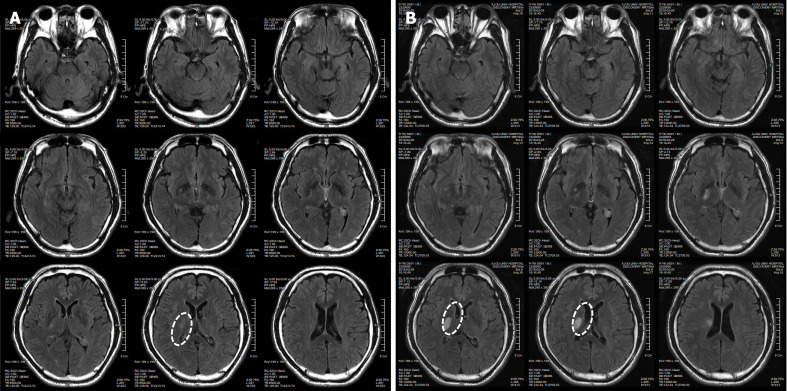

患者于2018年2月17日至18日出現(xiàn)暫時(shí)性無力癥狀,早上醒來后突發(fā)急性中風(fēng),導(dǎo)致左上肢和下肢癱瘓。患者在大學(xué)醫(yī)院急診室被診斷為Rt紋狀體囊性梗死(圖1A)。他于2018年3月2日出院,僅接受了阿司匹林處方,因?yàn)楦鶕?jù)腦計(jì)算機(jī)斷層掃描 (CT) 掃描,他的腦血管正常,盡管他的病情在住院期間惡化(圖1)。出院當(dāng)天,他被送往康復(fù)專科醫(yī)院接受長(zhǎng)期康復(fù)治療。然后他于2018年3月13日來韓國(guó)首爾生物美容與健康公司 (bBHC)-干細(xì)胞治療與研究所 (STRI)接受干細(xì)胞治療。